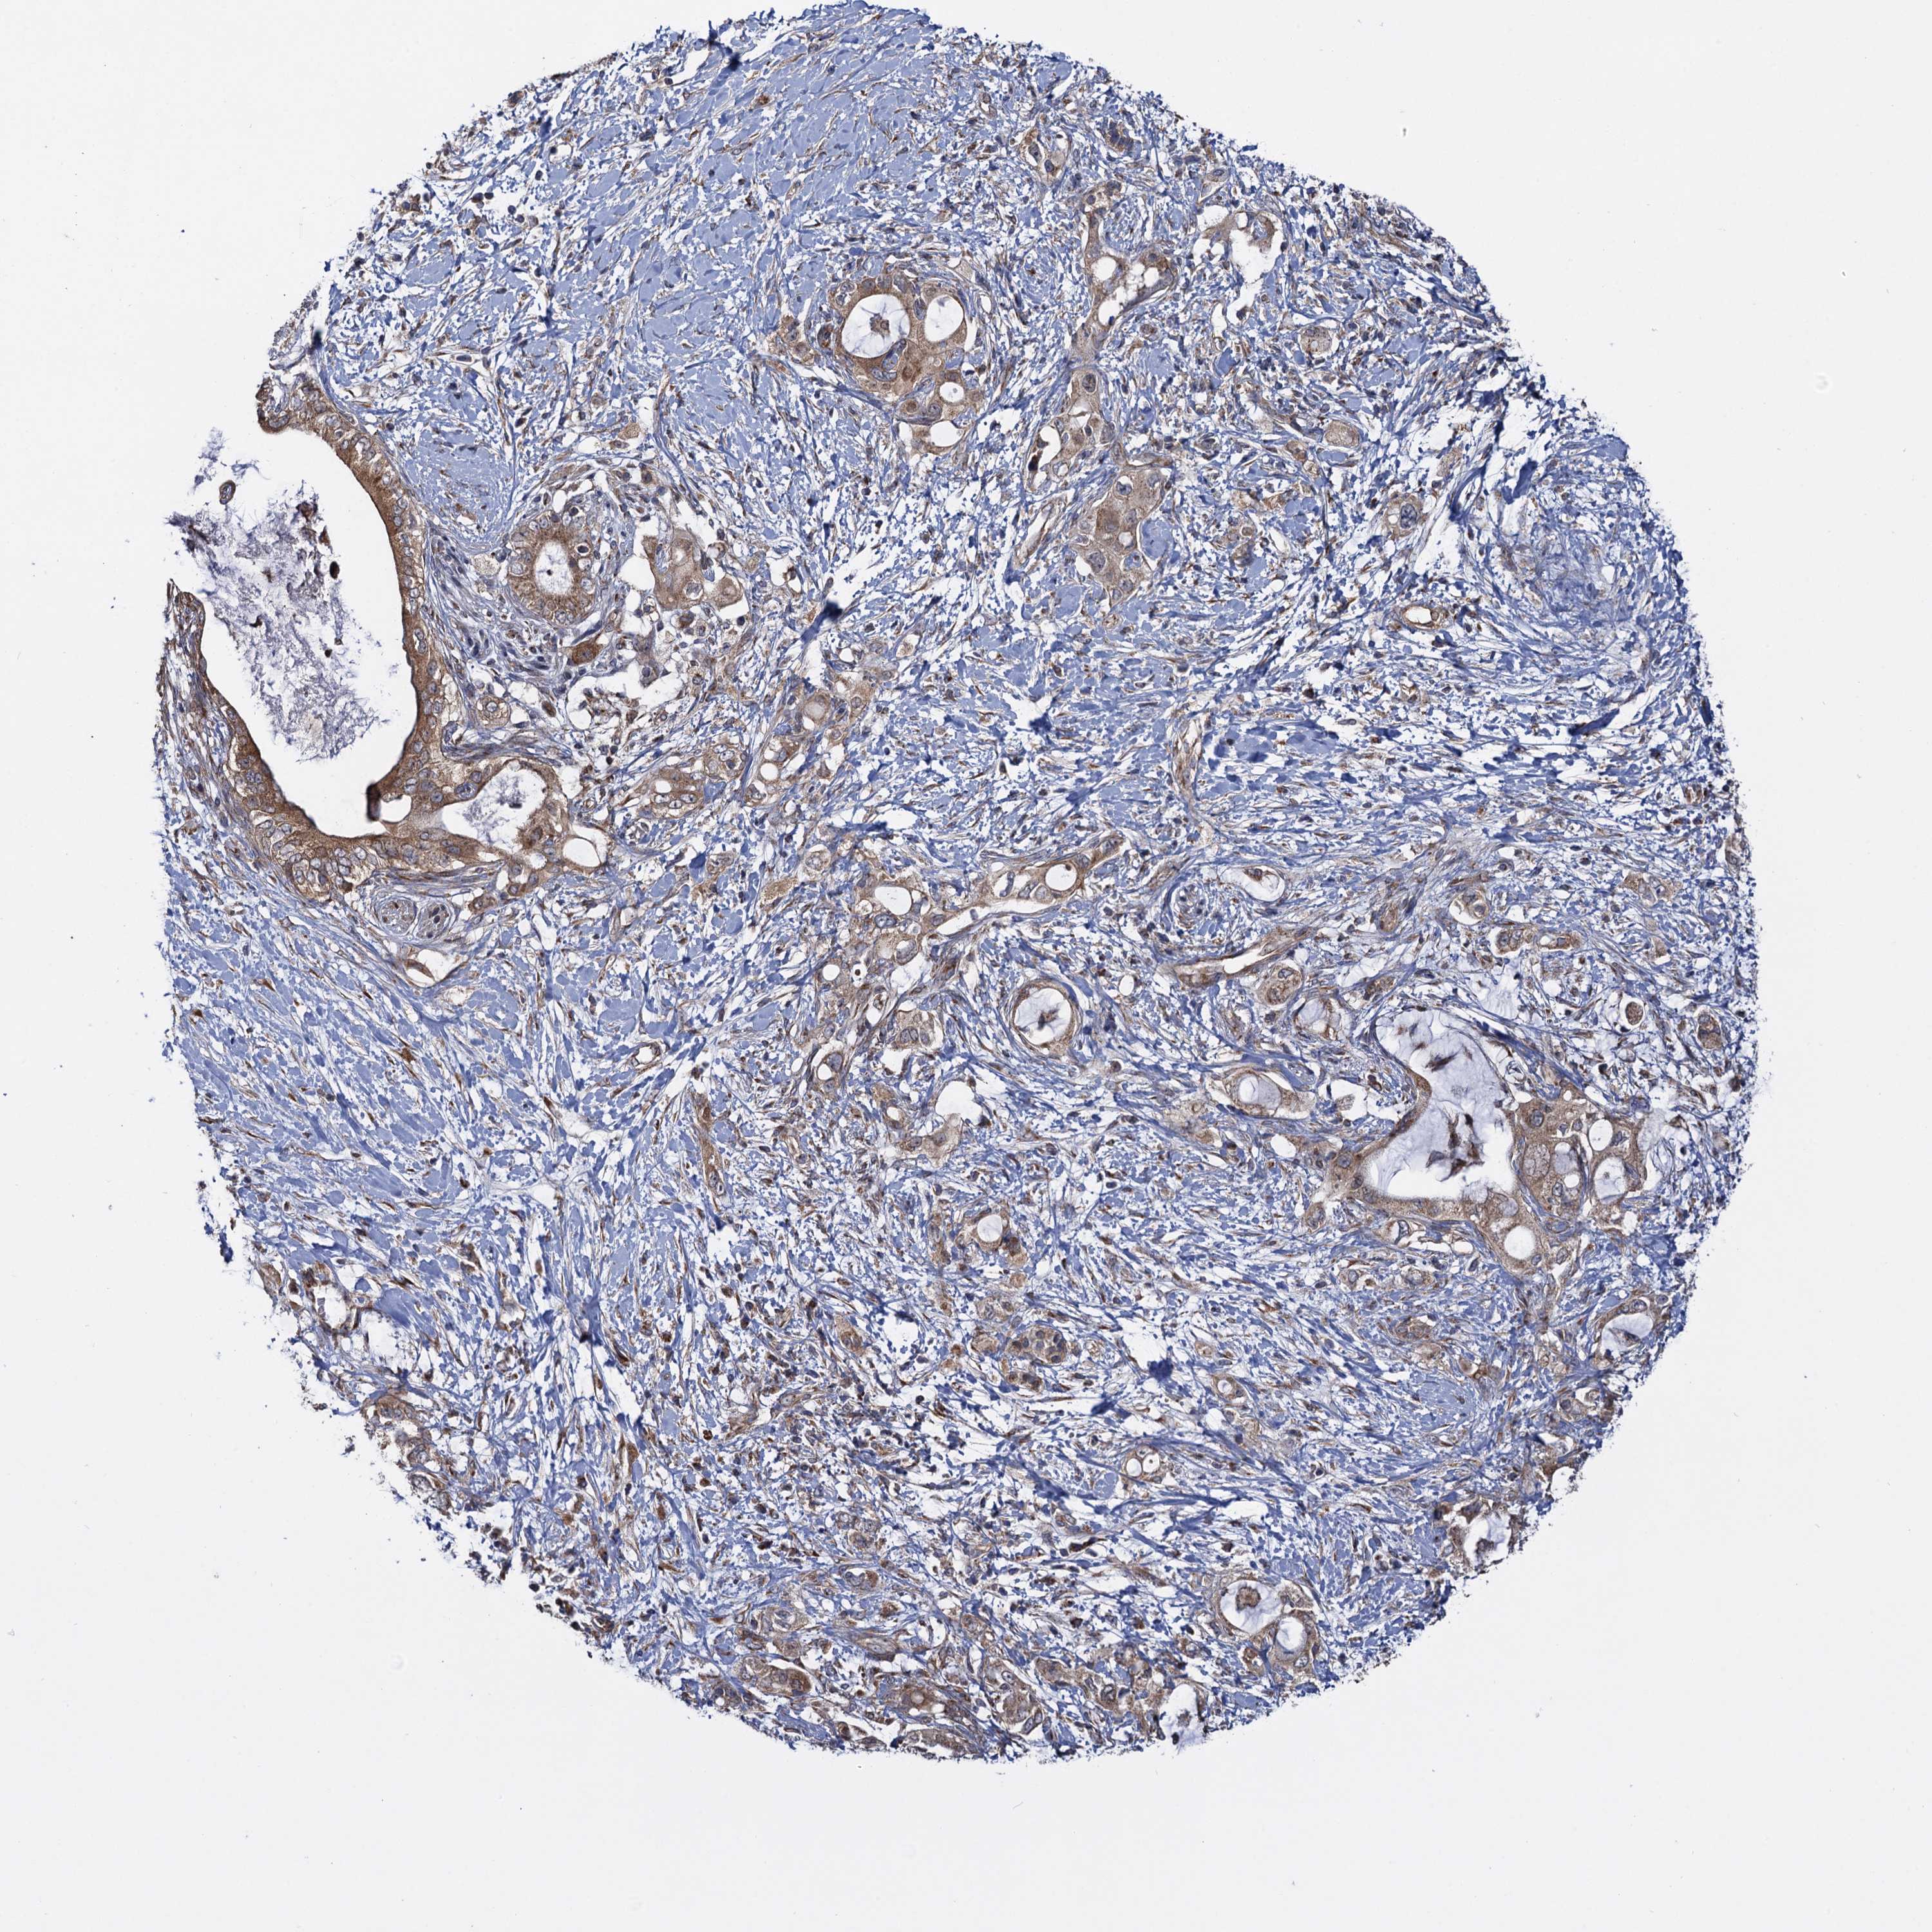

PANCREATIC CANCER - Protein expressioni

A mouse-over function shows sample information and annotation data. Click on an image to view it in a full screen mode. Samples can be filtered based on level of antibody staining by selecting one or several of the following categories: high, medium, low and not detected. The assay and annotation is described here.

Note that samples used for immunohistochemistry by the Human Protein Atlas do not correspond to samples in the TCGA dataset.

Antibody stainingi

Antibody staining in the annotated cell types in the current human tissue is reported as not detected, low, medium, or high, based on conventional immunohistochemistry profiling in selected tissues. This score is based on the combination of the staining intensity and fraction of stained cells.

Each image is clickable and will lead to virtual microscopy that enables deeper exploration of all samples and also displays staining intensity scores, fraction scores and subcellular localization as well as patient and tissue information for each sample.

Antibody HPA040601

Antibody HPA040652

Staining

High

Medium

Low

Not detected

Intensity

Strong

Moderate

Weak

Negative

Quantity

>75%

75%-25%

<25%

None

Location

Nuclear

Cytoplasmic/membranous

Cytoplasmic/membranous,nuclear

Adenocarcinoma, NOS